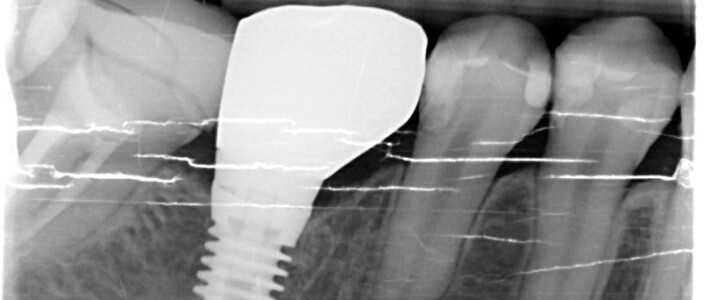

門牙牙套失敗後的植牙重建